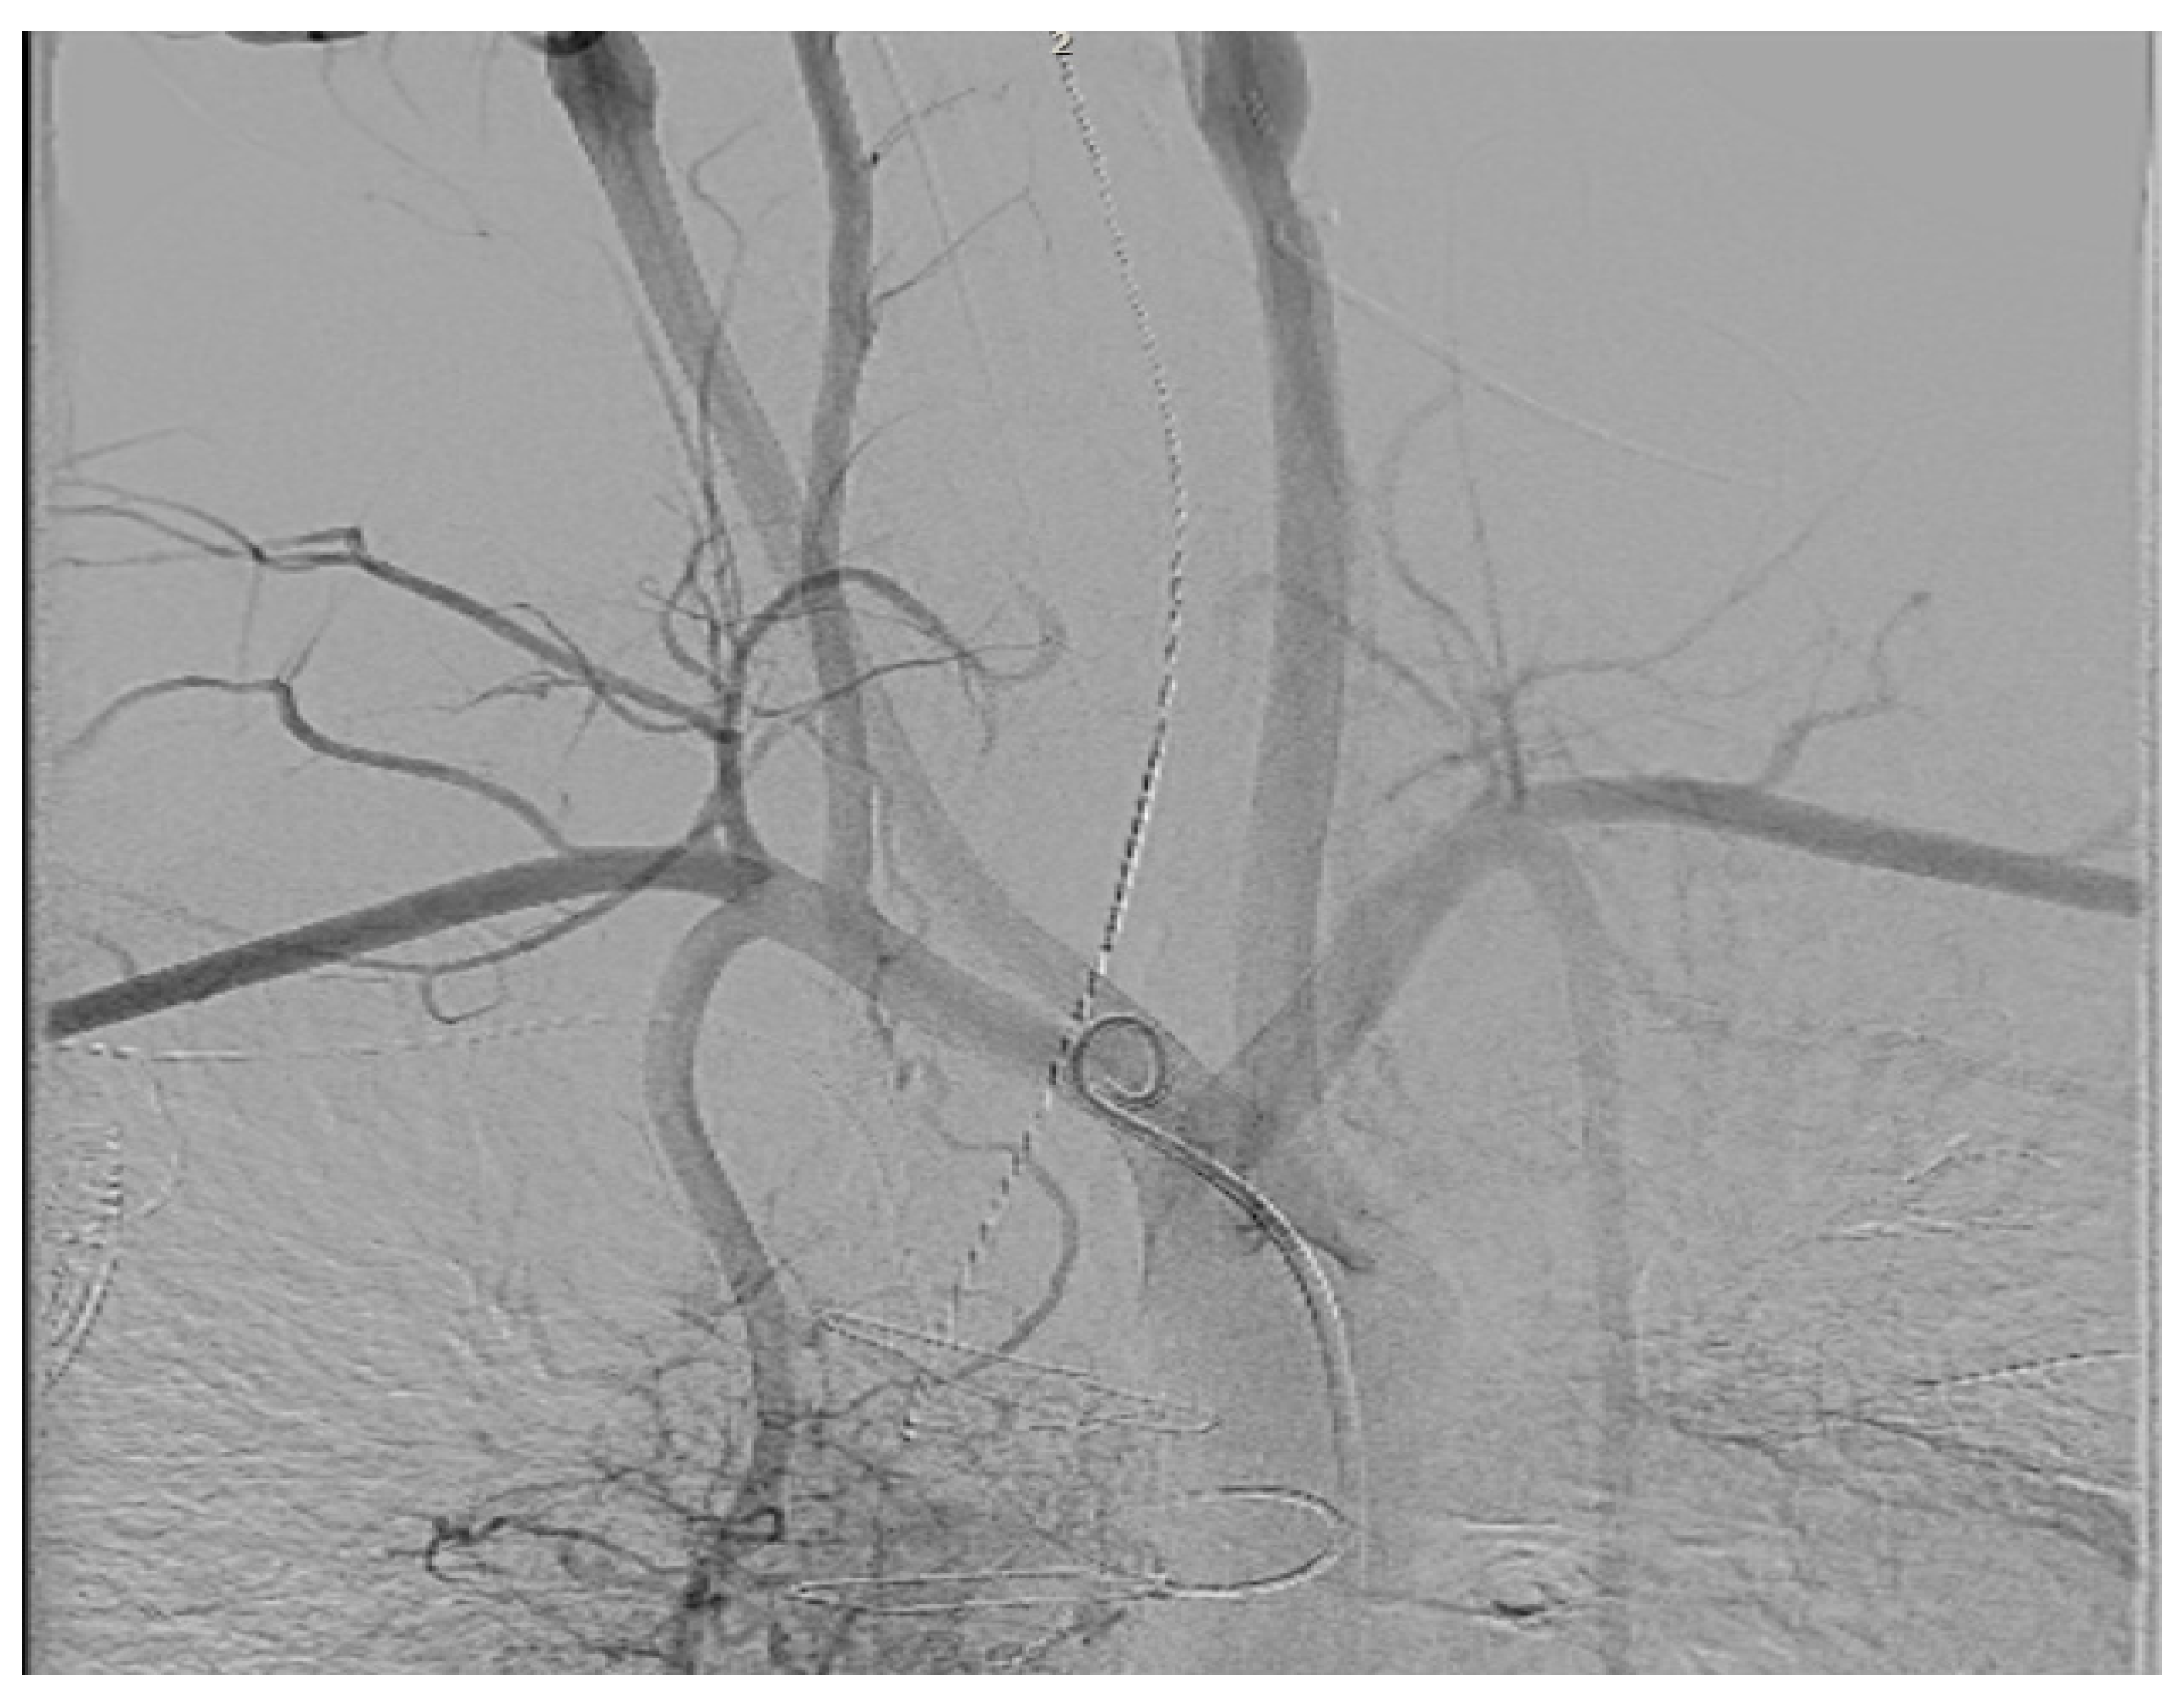

- Hayle, P.; Altayeb, F.; Hale, A.; Rao, A.; Ashrafi, R. Case report demonstrating novel approaches for leadless pacemaker implantation in the single ventricle heart. Eur. Heart J. Case Rep. 2025, 9, ytaf146. [Google Scholar] [CrossRef]

- Goulden, C.J.; Khanra, D.; Llewellyn, J.; Rao, A.; Evans, A.; Ashrafi, R. Novel approaches for leadless pacemaker implantation in the extra-cardiac Fontan cohort: Options to avoid leaded systems or epicardial pacing. J. Cardiovasc. Electrophysiol. 2023, 34, 2386–2392. [Google Scholar] [CrossRef]